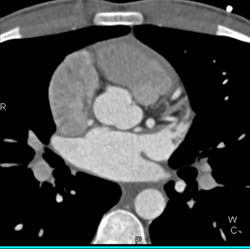

LAD Disease With Stenosis Less Than 50%